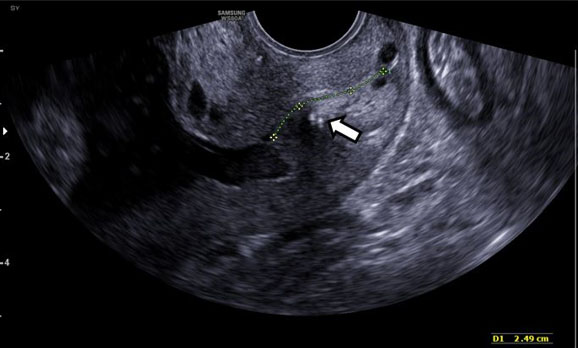

Postoperative ultrasound (at 22w2d) demonstrated CL of 2.7 cm without funneling and reduced sludge (Figure 4). Cervical length remained stable and the patient was asymptomatic until 27 weeks, when further cervical shortening to 1.2 cm was noted and antenatal corticosteroids were administered for fetal lung maturity. The couple greatly desired close outpatient surveillance rather than inpatient monitoring. Utilizing patient-centered decision making and to optimize timing of delivery, CL and tocometer were monitored weekly. At 34w0d, she underwent an uncomplicated planned Cesarean delivery because of vasa previa in the setting of pregnancy complicated by short cervix. The cerclage was removed after the completion of the cesarean section. She delivered a female neonate weighing 2310 g. The baby was admitted to the neonatal intensive care unit (NICU) on continuous positive airway pressure (CPAP). She was transitioned to room air by day 2 of life and received phototherapy for hyperbilirubinemia. Otherwise, the neonatal course was uncomplicated, and the baby was discharged on day 6. Gross placental examination showed velamentous cord insertion with intact fetal vessels running through the amniotic membranes (Figure 5).

Figure 4: Gray-scale examination of cervical length—Transvaginal sonogram with gray-scale examination of cervical length post-cerclage placement measuring 2.49 cm. Arrow indicates cerclage.